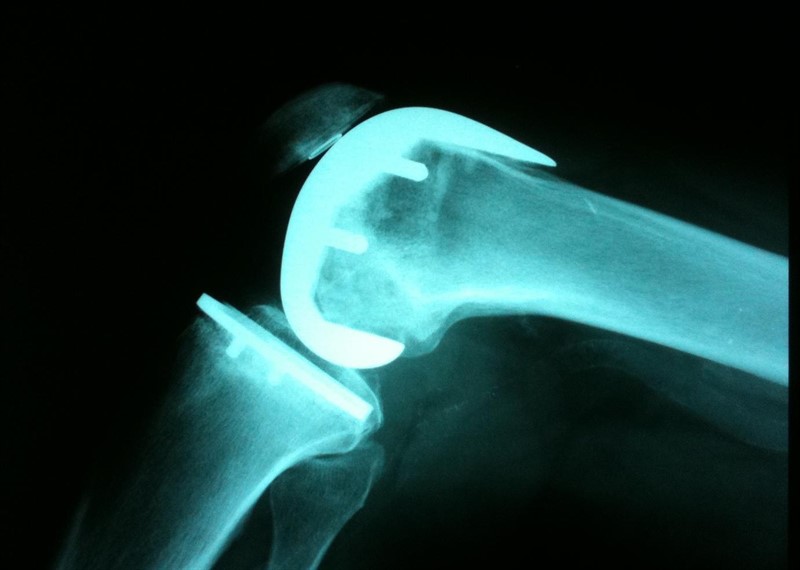

Paracetamol e ibuprofeno en la analgesia post reemplazo de cadera

14 febrero 2019